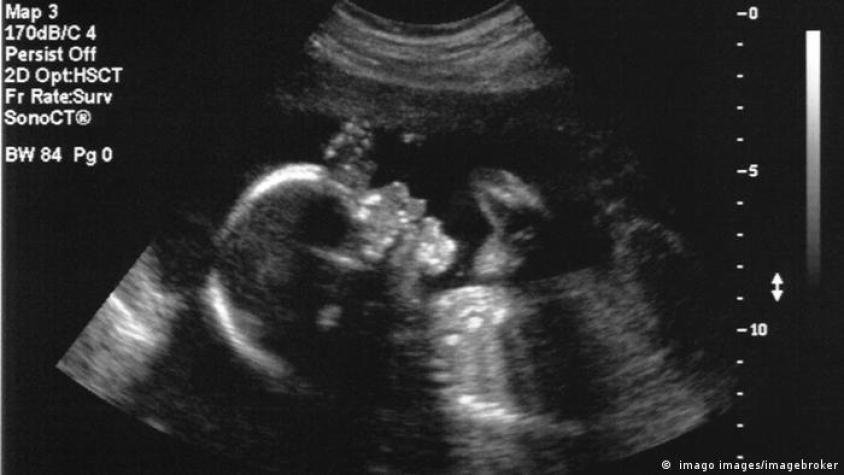

So, I came across this article about some doctors performing a successful surgery on a fetus’s brain. Crazy, right?

Apparently, the surgery was the first of its kind and was done to fix a rare condition where the baby’s skull wasn’t properly closing, which put pressure on the brain. The doctors were able to safely operate on the fetus while still in the womb, and both the mother and the baby are doing great.